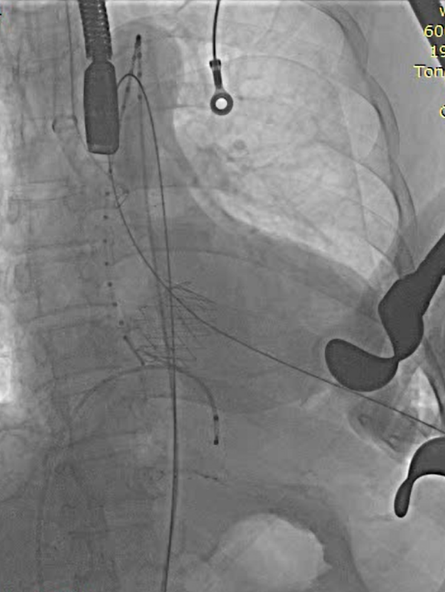

全麻后取仰卧位,消毒。取左前胸第5肋间切口进胸,腔镜辅助下游离左侧乳内动脉(LIMA)备用。肝素化。显露左前降支动脉(LAD),于其狭窄远段切开,将LIMA与之端侧吻合。血管桥排气后开放,测桥血流量满意。经股静脉植入心脏临时起搏器并确认正常工作。经股动脉置入造影导管至升主动脉根部,造影显示主动脉瓣大量反流,窦部结构可。3-0 Porlene线带毛毡片做荷包,经单弯导管引导超滑导丝至降主动脉,更换加硬导丝,导丝尖端于髂动脉分叉处。置入带主动脉瓣输送系统,造影定位下,准确释放29# J-Valve至主动脉瓣瓣环处,造影显示左右冠脉血流正常,TEE证实瓣膜位置可,未见明显反流。撤出输送系统,收紧荷包并缝合止血。放置胸管,逐层关闭各切口。

植入器进入升主动脉